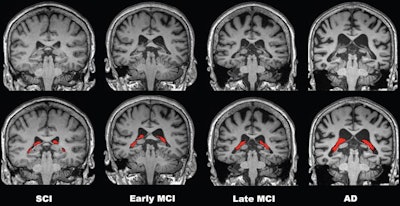

To elucidate this issue, the group analyzed imaging from a group of 532 patients with various stages of cognitive impairment due to Alzheimer's disease. Seventy-eight patients had subjective cognitive impairment (SCI), 158 had early mild cognitive impairment (MCI), 149 had late MCI, and 147 had Alzheimer's disease.

Comparisons of four representative 3-tesla brain MRI scans of choroid plexus (CP) volume (red) according to disease stage over the cognitive impairment spectrum. CP volume is greater in the patient with Alzheimer disease (AD) than in those with subjective cognitive impairment (SCI) or mild cognitive impairment (MCI). All patients were 75-year-old women. Image courtesy of Radiology.Results showed a stepwise increase in choroid plexus volume with severity of disease stage, with the SCI group having the smallest volumes and the Alzheimer's disease group having the largest. Moreover, the increase in choroid plexus volume was significantly associated with decreases in cortical and hippocampal volumes, which are more traditional markers of atrophy in Alzheimer's disease, according to the findings.